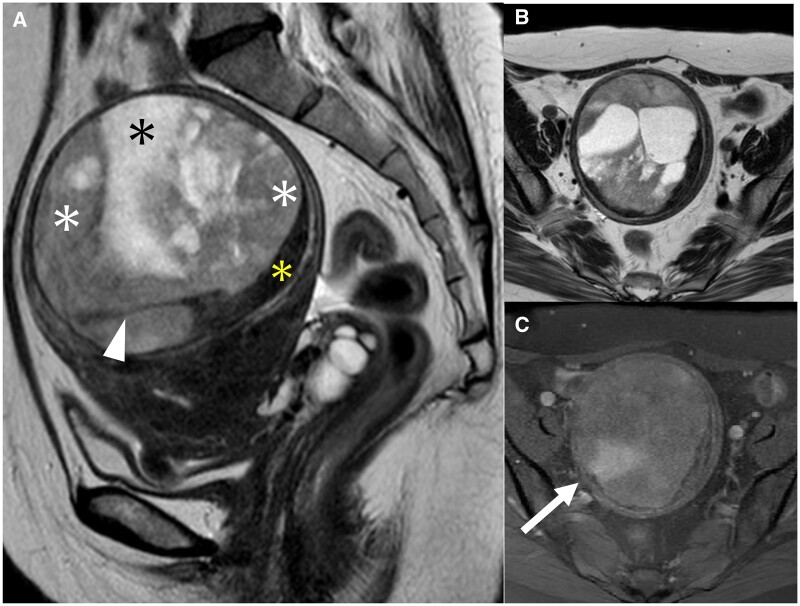

A low-grade endometrial stromal sarcoma (ESS) has a pattern of presenting as an intramyometrial mass and is often misdiagnosed as cellular leiomyoma or degenerative uterine leiomyoma. A low-grade ESS is a malignant tumour that requires total hysterectomy with bilateral salpingo-oophorectomy; while a leiomyoma is a benign tumour and could be acceptable for enucleation. As the treatment strategies differ between a low-grade ESS and leiomyoma, radiologists should be familiar with the characteristic MRI findings of a low-grade ESS. A 51-year-old woman with abnormal uterine bleeding had been observed for 2 years at a previous hospital for a uterine leiomyoma based on MRI findings. A contrast-enhanced MRI demonstrated an intramyometrial mass composed of three components with the hypointense rim on T2-weighted images (T2WI): the first component was a homogeneous solid structure with mild hyperintensity on T2WI with a low apparent diffusion coefficient value; the second component was cystic; the third component was a structure of low signal intensity on T2WI similar to the muscle. Although a degenerative uterine leiomyoma was a differential diagnosis, these MRI findings were suggestive of a low-grade ESS. A total abdominal hysterectomy, bilateral salpingo-oophorectomy, pelvic lymphadenectomy, and partial omentectomy were performed. The pathological diagnosis was a low-grade ESS. In a low-grade ESS, there are three major patterns of MRI findings: one of these patterns is the less popular but clinically important intramyometrial mass pattern, which can be misdiagnosed as a leiomyoma, and this case conformed to this pattern.